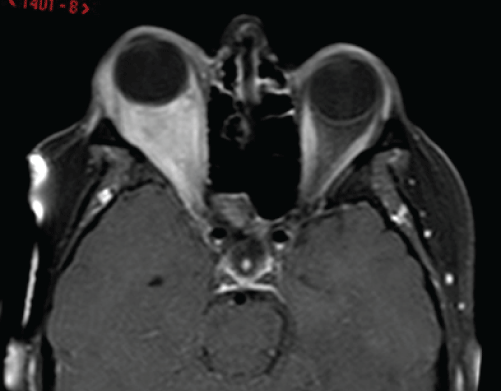

Supplemental Figure 2: Axial T1 post-contrast MRI sequence 22 months

following treatment with pentoxifylline and α-tocopherol, showing reduction in

the volume of the lesion that enhanced minimally and complete resolution of

proptosis. Reproduced with permission from BJOMFS [44].

View Supplemental Figure 2

The lesion initially responded to steroid therapy which was discontinued because it interfered with her diabetic control. An open biopsy showed a fibro-sclerotic lesion with B and T cell infiltration, increased IgG4+ plasma cells, up to 135/high power field, and IgG4+/IgG+ cell ratio of 41.8%, which confirmed the diagnosis of orbital IRD. The levels of serum IgG4 were not measured. Following a 22-month course of POF 800mg and AT 1,000IU orally twice daily, there was complete resolution of the symptoms and proptosis clinically (Figure 1B, Supplemental Figure 1B), as well as marked reduction of the lesion with minimal enhancement on repeat MRI scanning (Supplemental Figure 2).